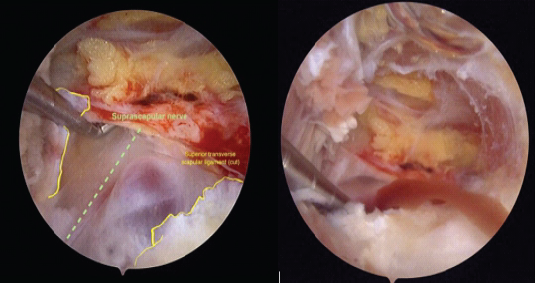

A 63-year-old right-handed woman with no relevant medical history presented with a 6-month history of continuous dull right shoulder pain, aggravated by lying on the affected side and associated with nocturnal pain. She reported functional limitations in overhead activities. Analgesics included paracetamol, ibuprofen, and topical diclofenac. Her regular physical activities included walking and cycling. Examination showed normal biceps and triceps reflexes, intact sensation, negative Spurling’s test, and preserved cervical and cervicodorsal mobility with negative facet joint and foraminal compression tests. Increased tone was noted in the postural muscles, mainly in the upper trapezius. Shoulder assessment revealed painless passive external rotation and abduction-external rotation, but active external rotation strength was reduced to 4/5 on the Medical Research Council scale. Impingement signs and Jobe’s test were negative. Palpation over the suprascapular notch elicited tenderness. Ultrasound revealed a cystic lesion posterior to the glenoid. Arthro-MRI confirmed a cyst from the spinoglenoid to the suprascapular notch along the course of the SSN. No teres minor atrophy was observed. Additional findings included insertional tendinopathy of the supraspinatus and a superoposterior labral tear. The imaging appearance was consistent with an intraneural ganglion cyst. Electromyography (EMG) showed a right SSN lesion at or proximal to the supraspinatus muscle branch, consistent with a partial axonotmesis and associated with moderate-to-severe muscular involvement. The patient initially opted for a conservative approach with physiotherapy, ultrasound-guided aspiration, and intralesional glucocorticoid injection for symptomatic relief (Depo-Medrol 80 mg). Aspiration of the cyst was attempted. However, only 1 mL of the thick mucinous fluid could be retrieved. At 4 weeks, pain improved but there was persistent fatigue with overhead activity and weakness in both the supraspinatus and infraspinatus. Ultrasound showed a persistent anechoic, lobulated cyst (9.4 × 7.6 mm) in the suprascapular notch, with extension to the spinoglenoid (4.1 × 7.4 mm) notch, without hyperemia. Physiotherapy was continued, with follow-up planned in 2 months. Two months later, ultrasound showed enlargement at the suprascapular notch (11.4 × 9.3 mm) and a stable size at the spinoglenoid notch (4.0 × 7.3 mm) (Fig. 2). EMG revealed improved compound muscle action potential (CMAP) amplitude and recruitment in the supraspinatus, but decreased recruitment and denervation in the infraspinatus. A surgical indication was made for arthroscopic decompression of the cyst at both the suprascapular and spinoglenoid notches and treatment of the labral tear. Arthroscopy revealed a degenerative type IIB superior labrum anterior to posterior (SLAP) lesion, treated with biceps tenotomy and labral debridement, as repair was deemed infeasible. Cyst decompression exposed a well-defined synovial cyst wall surrounding the nerve. Incision released a wine-red mucinous fluid, and the wall was carefully debrided to achieve complete decompression (Fig. 1)

Figure 3: Arthroscopic view before (left) and after (right) the incision. This figure illustrates a suprascapular ganglion cyst causing suprascapular nerve compression at the suprascapular notch. Upon incision, a wine-red mucinous fluid was released. Yellow line: superior transverse scapular ligament (cut). Green dotted line: suprascapular nerve.